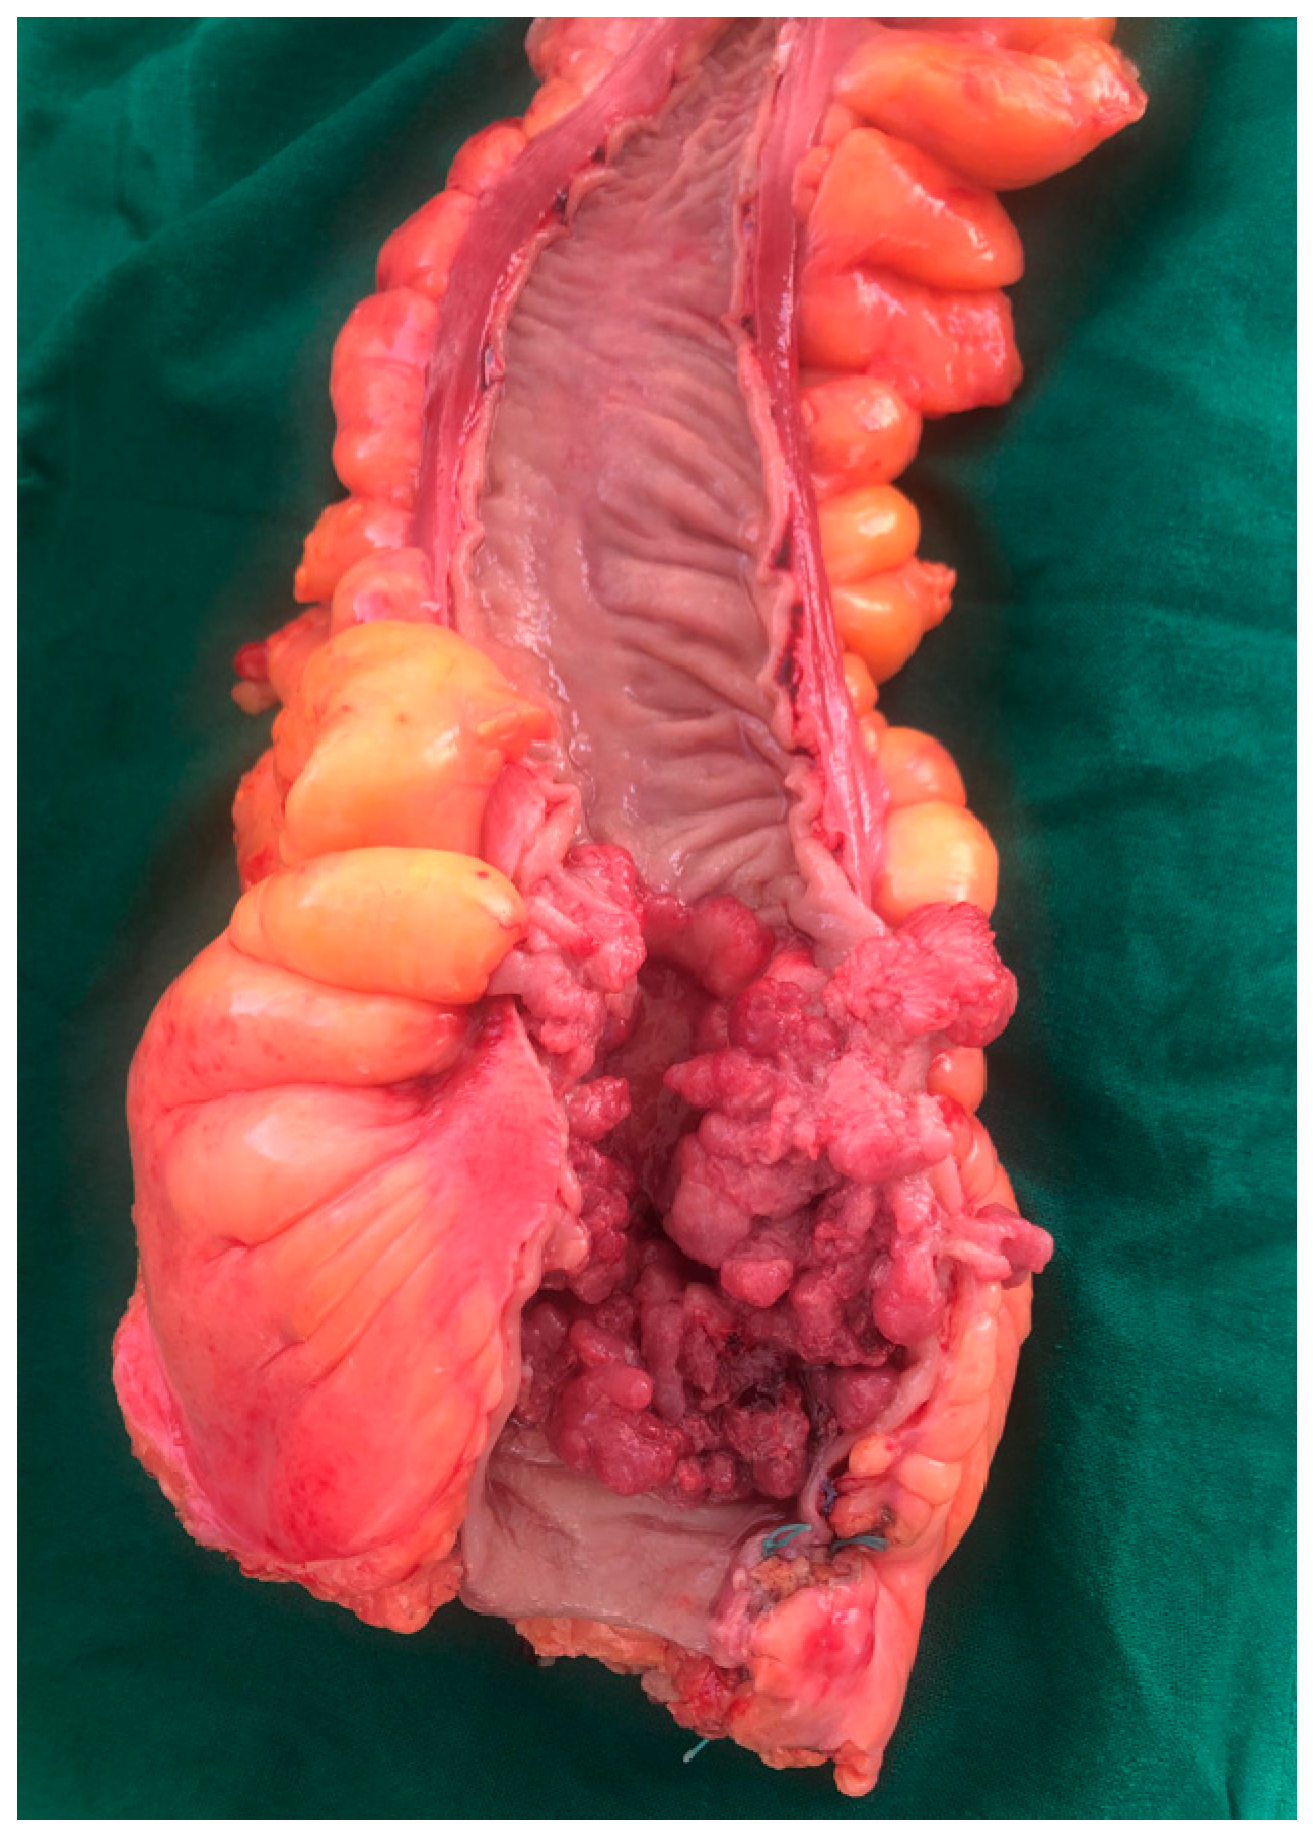

4.1.6. Tumor Morphopathology